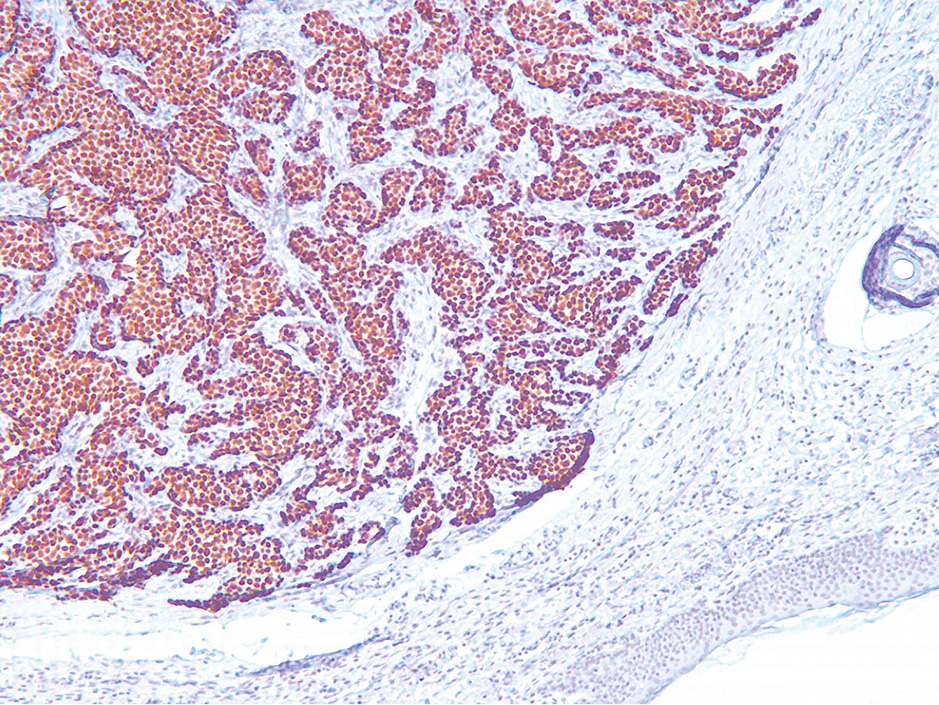

Рис. 3. Иммуногистохимическое исследование операционного материала. Диффузная сильная ядерная экспрессия ER в клетках опухоли, ×10.

Fig. 3. Immunohistochemical examination of the surgical specimen. Diffuse strong nuclear ER expression in tumor cells, ×10.

При иммуногистохимическом исследовании клетки опухоли сильно и диффузно экспрессируют рецепторы эстрогенов – ER (рис. 3), слабо и диффузно рецепторы прогестерона (рис. 4), а также сильно и очагово-диффузно раково-эмбриональный антиген – СЕА (рис. 5) и антиген эпителиальных мембран (ЕМА). Индекс пролиферативной активности Ki67 менее 20% (рис. 6), а рецептор эпидермального фактора роста человека 2-го типа Her2 – отрицательный. Опухоль не экспрессирует цитокератины СК 5/6, Р63 и маммаглобин.